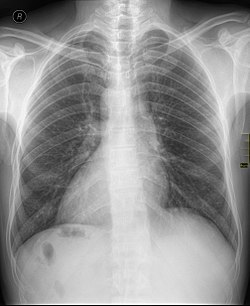

- Рентгенография органов грудной полости — в основном делается в переднезадней проекции и тогда становятся видны структурные изменения по типу декстракардии, кардиомегалии. Также может отмечаться увеличение правого предсердия, узкий сосудистый пучок и пр.

- Рентгеновские методы – оценивается расположение и размеры сердца, а также состояние легочных сосудов, это дополнительный способ диагностики при подозрении на ВПС.